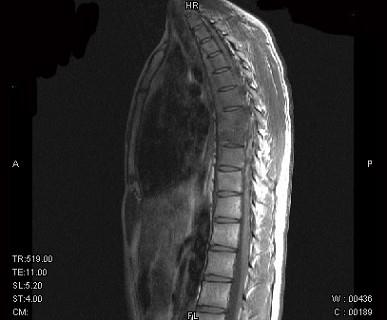

问题 男,21岁,有午后发热,夜间盗汗等,胸部疼痛,活动时加重,休息后减轻,请结合所提供图像,选择最佳答案 ( )

选项 A、骨巨细胞瘤 B、胸椎结核 C、胸椎骨转移 D、胸椎退行性变 E、骨髓瘤

答案 B